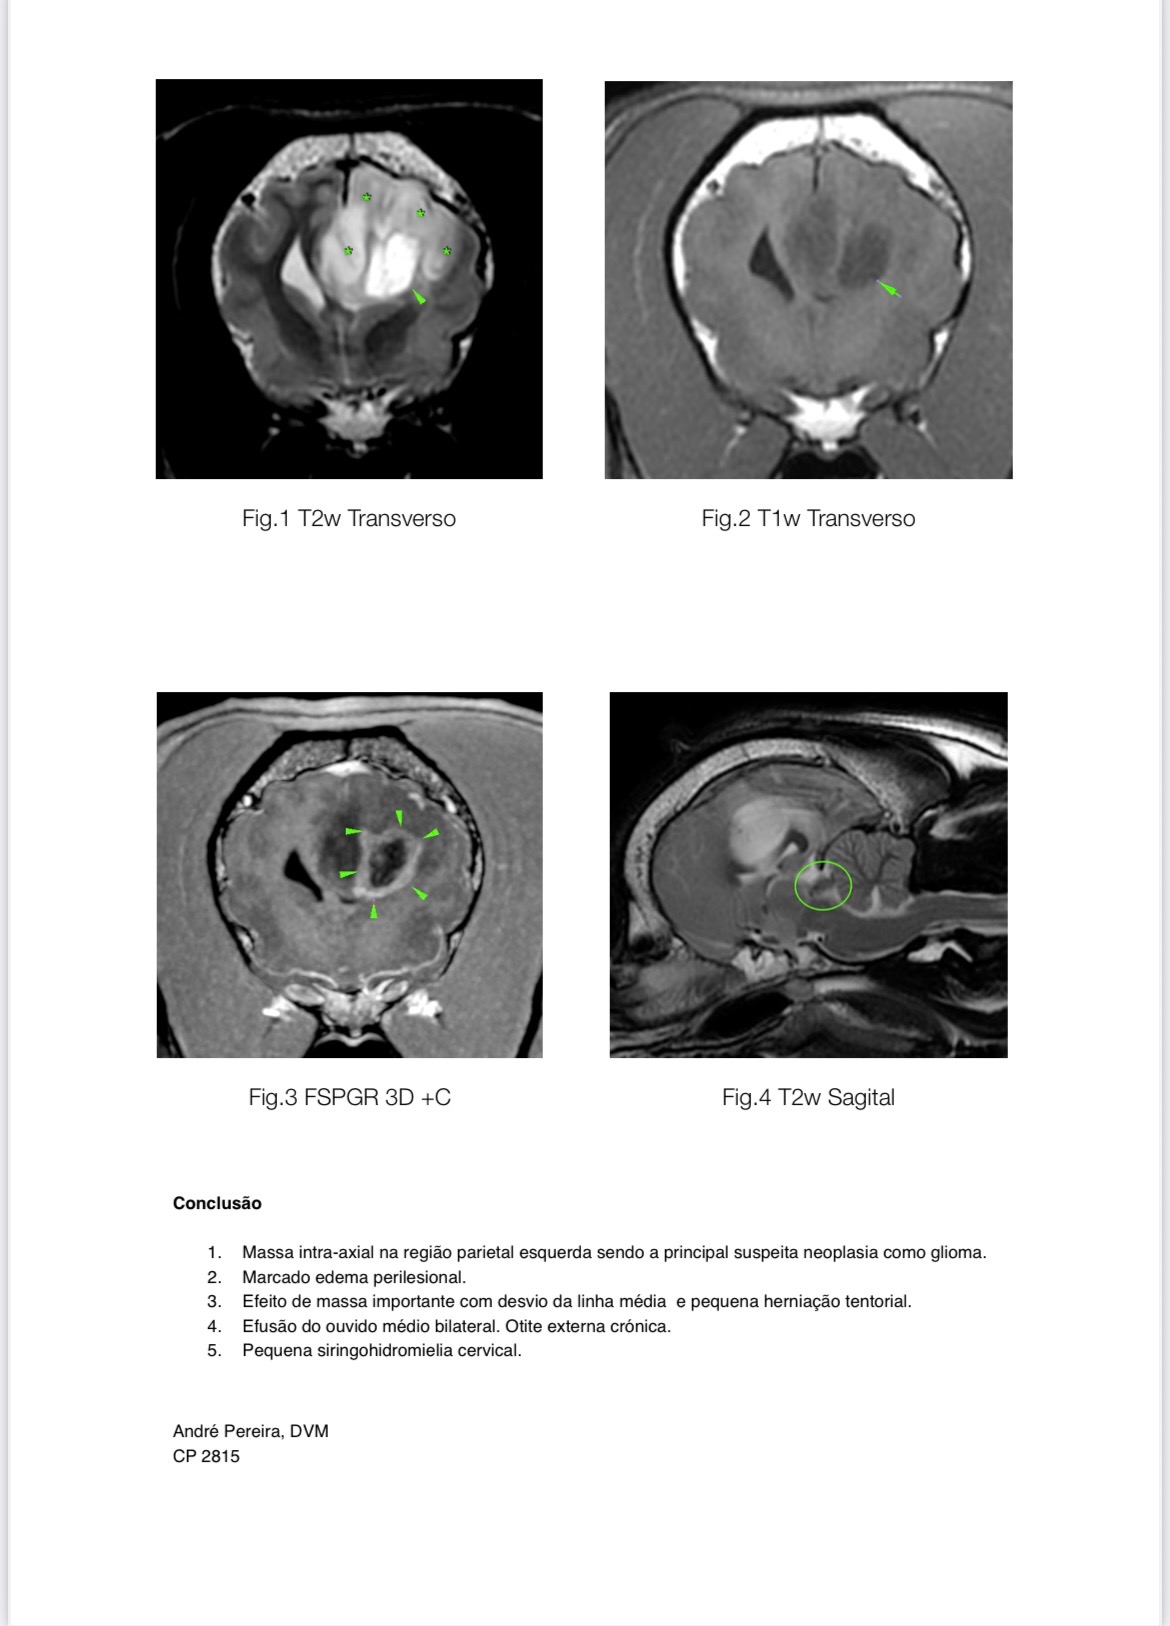

A couple of months ago, Woody began having seizures. At first, they were mild, but they quickly became more frequent and severe. After a long and terrifying seizure that lasted for hours, he was rushed to the hospital. Tests showed what we feared most: a brain tumor, with severe inflammation and swelling.

Surgery isn’t possible. But radiotherapy could give him a chance.